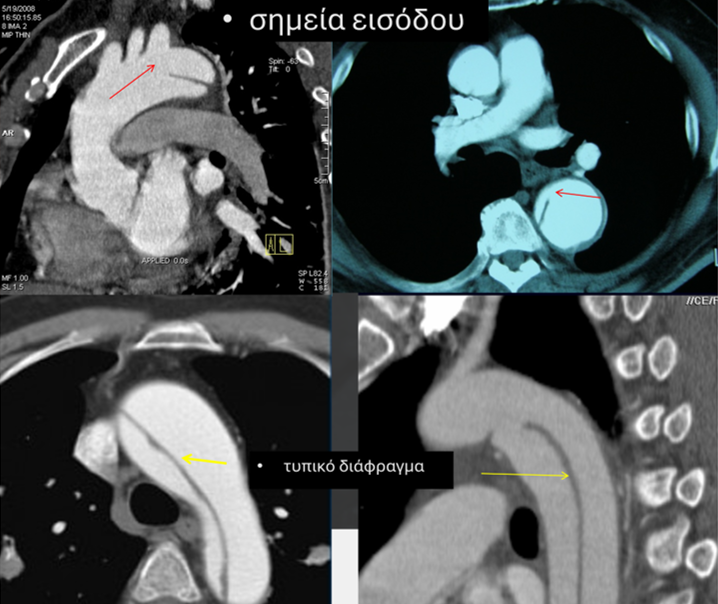

Κατά την αντιμετώπιση του αορτικού διαχωρισμού σε οξεία αλλά κυρίως χρόνια βάση η ενδαγγειακή χειρουργική αποτέλεσε σανίδα σωτηρίας τα τελευταία χρόνια καθώς μείωσε δραματικά τη θνητότητα του χειρουργείου. Παρά την ουσιαστική πρόοδο στη θεραπευτική μας προσέγγιση ακόμη και σήμερα, παραμένει μεγάλη δυσκολία στην ενδαγγειακή αντιμετώπιση της πάθησης η αναγνώριση του αληθούς αυλού, η αναγνώριση του αρχικού σχισίματος (σημείο εισόδου), η επέκταση του διαφράγματος που χωρίζει τους δύο αυλούς και φυσικά η τοποθέτηση του ενδομοσχεύματος στον αυλό εκείνο που τροφοδοτεί τα σπλαχνικά αγγεία.

Σε όλη αυτή την προσπάθεια μεγάλη δυσκολία δημιουργεί συχνά το διάφραγμα (septum) που χωρίζει τους δύο αυλούς καθώς ενίοτε κάποια από τα τέσσερα σπλαχνικά αγγεία μπορεί να αιματώνονται από τον ψευδή πλέον αυλό, άρα η τοποθέτηση ενδομοσχεύματος στον αληθή και η εξάλειψη του ψευδούς θα προκαλούσε διακοπή της αιμάτωσης σε κάποιο σπλαχνικό αγγείο με καταστροφικές επιπλοκές. Σήμερα έχουμε τη δυνατότητα να εφαρμόσουμε τεχνική διατομής του διαφράγματος ώστε να φέρουμε σε επικοινωνία περιφερικά τους δύο αυλούς και με την τοποθέτηση του ενδομοσχεύματος στον αληθή να μην διαταράξουμε την αιμάτωση καμίας σπλαχνικής αρτηρίας (σχημ 3).

Η τεχνική βασίζεται στην τοποθέτηση σύρματος 0,014” από τα πόδια και από τον αληθή στον ψευδή αυλό διαμέσου του σημείου εισόδου στον ψευδή αυλό. Το σύρμα στο σημείο που ακουμπάει το διάφραγμα απογυμνώνεται ώστε να μεταφέρει το ρεύμα της διαθερμίας, ενώ πριν και μετά προστατεύεται με πλαστικούς καθετήρες για να μην τραυματίσει την αορτή. Τα άκρα του σύρματος συνδέονται στη διαθερμία και υπό ακτινοσκόπηση εκτελείται η σεπτοτομή δηλ η διατομή του διαφράγματος.